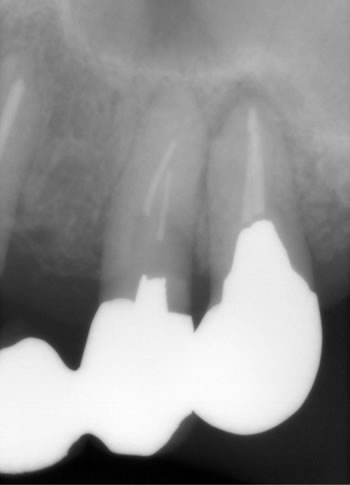

1枚目のレントゲンの患者様も半年前に歯肉が腫れて原因が不明でお薬で消炎して様子をみてもらっていました、、、

お久しぶりに来院されまして、また腫れたそうですが、、、 |

確認でもう一度レントゲンで撮影しますと、、、

なるほど割れている!!!

ここまで「真っ2つ」に割れているとレントゲンで解りやすいですよね!

おそらく想像ですが、半年前の腫れた時点で既に亀裂(クラック)はあったのでしょうが、レントゲンでも確認が難しかったのです。

亀裂は次第に大きくなり、割れとなり判明するのです! |